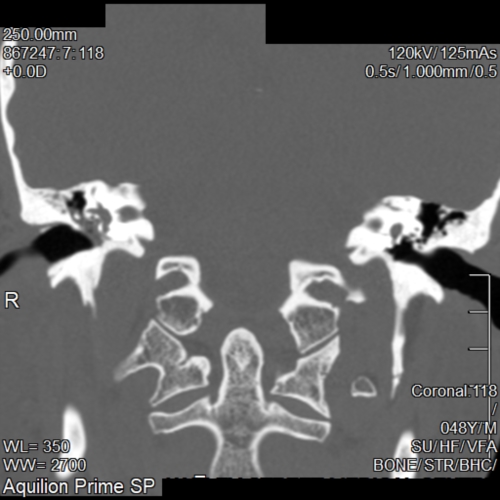

He also recommended a CT scan of the ears.

The CT scan report came back saying I had Chronic Otomastoiditus and showed opacification of the Mastoid bone and middle ear space. (See pictures)

I think I can see thickening of the of the right ear drum. But I'm not 100% sure. Maybe any curious radiologists out there can correct me. The right middle ear space is opacified so I find it difficult to see any obvious changes to the ossicular chain.

The ENT doctor thought it was chronic inflammation due to Eustachian tube dysfunction and suggested inserting a T-Tube and performing a balloon dilation, I opted out of the balloon dilation due to my occasional patulous eustachian tube (Really the ENT doctor should have flagged this up before recommending it!).

I was told that it would take a while for the middle ear inflammation to go away (6months to a year!) He also said that my right ear drum was sclerotic and rigid and my hearing would never be the same as my left ear. He said the ossicular chain (stapes,incus,malleaus) was fine and not damaged.

I’m not sure this can be true though as normally Myringosclerosis (ear drum sclerosis) doesn’t effect hearing. Whereas Tympanosclerosis effects the ear drum and ossiclular chain.